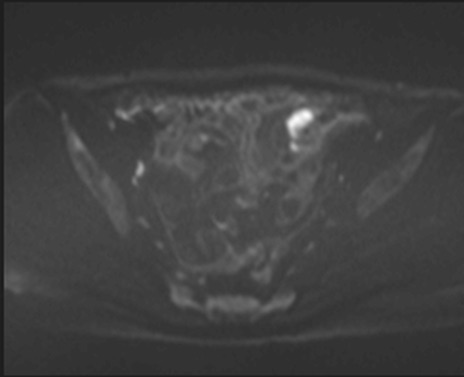

症例39 DWI/ADC

MRI(4日後)